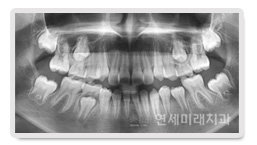

È¥ÇÕÄ¡¿±â ¾î¸°À̵鿡°Ô ÀÖ¾î¼, ¿µ±¸Ä¡°¡ ¸ÍÃâÇÒ °ø°£ÀÌ ºÎÁ·ÇÑ °æ¿ì °¡Àå ÈçÇÏ°Ô ³ªÅ¸³ª´Â Áõ»óÀº À§Åμ۰÷´Ï°¡ À߸ø ³ª¿À´Â °ÍÀÔ´Ï´Ù. À§ÅÎ ¼Û°÷´Ï´Â ¸¸ 11-12¼¼°æ¿¡ ¸ÍÃâÇÏ°Ô µÇ¸ç Å« ¾î ±Ý´Ï ¾ÕÂÊ¿¡¼´Â °¡Àå ³ªÁß¿¡ ³ª¿À´Â Ä¡¾ÆÀÔ´Ï´Ù. µû¶ó¼ À§Åο¡¼ ¿µ±¸Ä¡°¡ ³ª¿Ã °ø°£ÀÌ ºÎÁ· ÇÑ °æ¿ì »çÁø¿¡¼ º¸½Ã´Â °Íó·³ ¼Û°÷´Ï°¡ »ß¶Ô°Ô¸ÍÃâÇÏ°Ô µË´Ï´Ù. ¿µ±¸Ä¡°¡ ³ª¿Ã °ø°£ÀÌ ºÎÁ·ÇÑ °æ¿ì Ä¡·áÀÇ ÀÏÂ÷ÀûÀÎ ¸ñÇ¥´Â ¸ðµç ¿µ±¸Ä¡°¡ ±¸°³»·Î ³ª¿Ã ¼ö ÀÖ ´Â ȯ°æÀ» ¸¸µé¾îÁÖ´Â °ÍÀÔ´Ï´Ù. ¸ðµç ¿µ±¸Ä¡°¡ ±¸°³»·Î ¸ÍÃ⠵Ǿú´Ù¸é ¹Ù¶÷Á÷ÇÑ À§Ä¡¿¡ ¹è¿ ÇÏ°Ô µË´Ï´Ù. À̶§ ÇÊ¿äÇÑ °ø°£ÀÇ ¾ç, °ñ°Ý¹× ±³ÇÕ°ü°è, ³²¾ÆÀÖ´Â ¼ºÀå·®µîÀ» °í·ÁÇÏ¿© Ä¡·á¸¦ °áÁ¤ÇϰԵ˴ϴÙ.

¿µ±¸Ä¡°¡ ³ª¿Ã °ø°£ÀÌ ºÎÁ·ÇÏ´Ù°í ÇØ¼ ¹Ýµå½Ã ¹ßÄ¡¸¦ ÇØ¾ßÇÏ´Â °ÍÀº ¾Æ´Ï¸ç ¼ºÀåÀÌ ³²¾ÆÀÖ´Â ¾î¸°À̵éÀÇ °æ¿ì °ø°£À» È®º¸ÇÒ ¼ö ÀÖ´Â ¹æ¹ýÀÌ ¸¹±â ¶§¹®¿¡ »çÁø¿¡¼ º¸½Ã ´Â Áõ·Ê¿¡¼¿Í °°ÀÌ Ä¡¾Æ¸¦ »©Áö ¾Ê°íµµ ÁÁÀº °á°ú¸¦ ¾òÀ» ¼ö ÀÖ´Â °æ¿ì°¡ ´õ ¸¹ÀÌ ÀÖ½À´Ï´Ù.

À¯Ä¡ (Á¥´Ï)´Â ¿µ±¸Ä¡°¡ ³ª¿À±â Àü±îÁö ¾Ã¾î¸Ô°í ¹ßÀ½ÇÏ´Â ±â´É ¿Ü¿¡µµ ¿µ±¸Ä¡°¡ Á¦ÀÚ¸®¿¡ ³ª¿Ã ¼ö ÀÖµµ·Ï °ø°£À» È®º¸ÇØ ÁÖ´Â Áß¿äÇÑ ±â´ÉÀÌ ÀÖ½À´Ï´Ù. À¯Ä¡°¡ Á¶±â¿¡ ºüÁö°Å³ª, ³Ê¹« ´Ê°Ô ºüÁö´Â °Í ¸ðµÎ ¿µ±¸Ä¡ÀÇ ¸ÍÃâ¿¡ ¿µÇâÀ» ¹ÌÄ¡°Ô µË´Ï´Ù. À¯Ä¡¿¡ ¹ß»ýÇÑ ÃæÄ¡¸¦ Á¦¶§¿¡ Ä¡·áÇÏÁö ¸øÇϸé, À¯Ä¡°¡ ¿¹Á¤º¸´Ù Á¶±â¿¡ Å»¶ôÇÒ °¡´É¼ºÀÌ ³ô¾ÆÁö¸ç ÀÌ´Â ¿µ±¸Ä¡ ¸ÍÃâ¿¡ ÇÊ¿äÇÑ °ø°£ÀÇ ¼Ò½Ç·Î À̾îÁ® À§ »çÁø°ú °°ÀÌ ¾î±Ý´ÏºÎÀ§¿¡¼ ¿µ±¸Ä¡°¡ »ß¶Ô°Ô ³ª¿À°Å³ª ½ÉÇÑ °æ¿ì ¸ÍÃâÇÏÁö ¸øÇÒ ¼öµµ ÀÖ½À´Ï´Ù. À̸¦ ¿¹¹æÇϱâ À§Çؼ´Â À¯Ä¡¿¡ ¹ß»ýÇÏ´Â ÃæÄ¡¸¦ Á¦¶§¿¡ Ä¡·áÇØ ÁÖ¾î¾ß Çϸç, ÃæÄ¡·Î ÀÎÇØ¼ À¯Ä¡¸¦ ¹ßÄ¡ÇÏ°Ô µÇ´Â °æ¿ì¿¡´Â Ä¡°ú¿¡ ¿À¼Å¼ »ó´ãÀ» ¹ÞÀ¸½Ã´Â °ÍÀÌ ÁÁ½À´Ï´Ù.

¹Ý´ë·Î À¯Ä¡°¡ ºüÁ®¾ß ÇÒ ½Ã±â°¡ Áö³ª¼µµ ºüÁöÁö ¾Ê°í ³²¾ÆÀÖ´Â °æ¿ì¿¡µµ ¹®Á¦°¡ µÉ ¼ö ÀÖ½À´Ï´Ù. ÀûÀýÇÑ ½Ã±â¿Í ¼ø¼¿¡ ¸Â°Ô ¿µ±¸Ä¡·Î ±³È¯µÇ¾î¾ß Çϴµ¥ À¯Ä¡°¡ ºüÁöÁö ¾Ê°í ³²¾ÆÀÖ´Â °æ¿ì¿¡´Â ¿µ±¸Ä¡ÀÇ ¸ÍÃâÀ» ¹æÇØÇÒ ¼öµµ ÀÖ½À´Ï´Ù. À̸¦ ¸¸±âÀÜÁ¸ À¯Ä¡¶ó°í Çϴµ¥ ¿øÀÎÀº ¿©·¯ °¡Áö°¡ ÀÖÀ¸¸ç, °Ë»ç¸¦ ÅëÇØ ¿øÀÎÀ» ÆÄ¾ÇÇÏ°í ¿µ±¸Ä¡ÀÇ ¸ÍÃâ ÀáÀç·ÂÀÌ ³²¾ÆÀÖÀ» ¶§ À¯Ä¡¸¦ ¹ßÄ¡ÇØ ÁÖ´Â °ÍÀÌ ÁÁ½À´Ï´Ù.